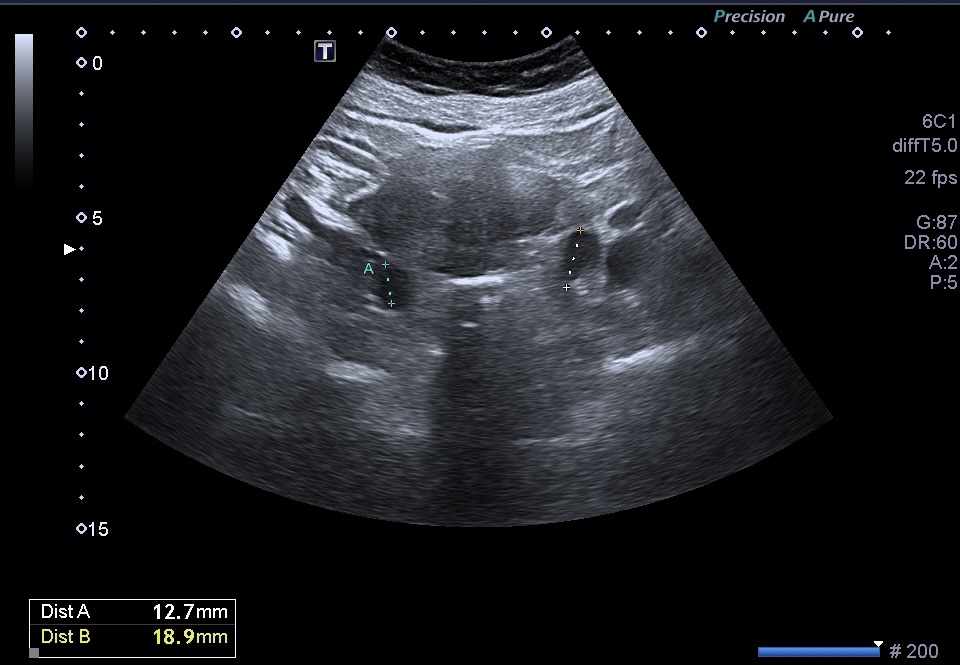

Medidas

2. Tamaño: El tamaño de un urotelioma puede variar desde pequeñas lesiones hasta masas más grandes que ocupan una parte significativa de la vejiga.